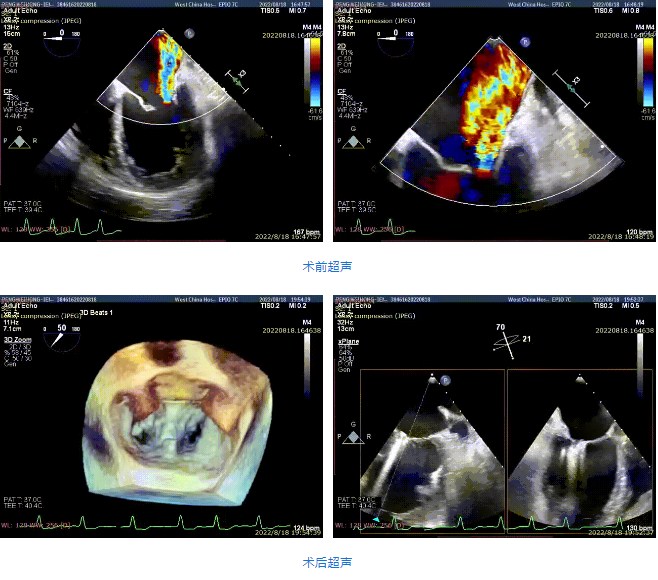

接受治療的是一例59歲男性患者,主訴“心累氣促5余年,加重伴胸痛1個多月”,已經(jīng)過規(guī)范化藥物治療。術(shù)前超聲提示左心明顯增大,右心稍大。左室心尖部肌小梁增多。室間隔及左室后壁厚度正常,左室后下壁基底段變薄、稍向外膨出,搏幅明顯減弱,余室壁搏幅減低,左室壁整體運動欠協(xié)調(diào)。二尖瓣瓣尖稍增厚,回聲稍增強(qiáng),后瓣受牽拉,活動度差,前瓣關(guān)閉錯位,開放尚可。多普勒提示:二尖瓣大量反流(VC=6*18mm,EOA=0.53cm2,Vol=61ml);二尖瓣環(huán)舒張期運動頻譜呈單峰,EF=30%。

手術(shù)采用全身麻醉插管,經(jīng)股靜脈-房間隔入路,在TEE和DSA引導(dǎo)下完成房間隔穿刺。置入瓣膜夾系統(tǒng)后,在左房調(diào)整瓣膜夾的位置和軸向,后進(jìn)入左室,在TEE引導(dǎo)下捕捉二尖瓣前后瓣葉,并關(guān)閉瓣膜夾。經(jīng)TEE反復(fù)確認(rèn)手術(shù)效果后最終鎖定并釋放瓣膜夾。術(shù)后即刻超聲顯示瓣膜夾位置穩(wěn)定,功能良好,肺靜脈逆流和左房壓都明顯好轉(zhuǎn)。